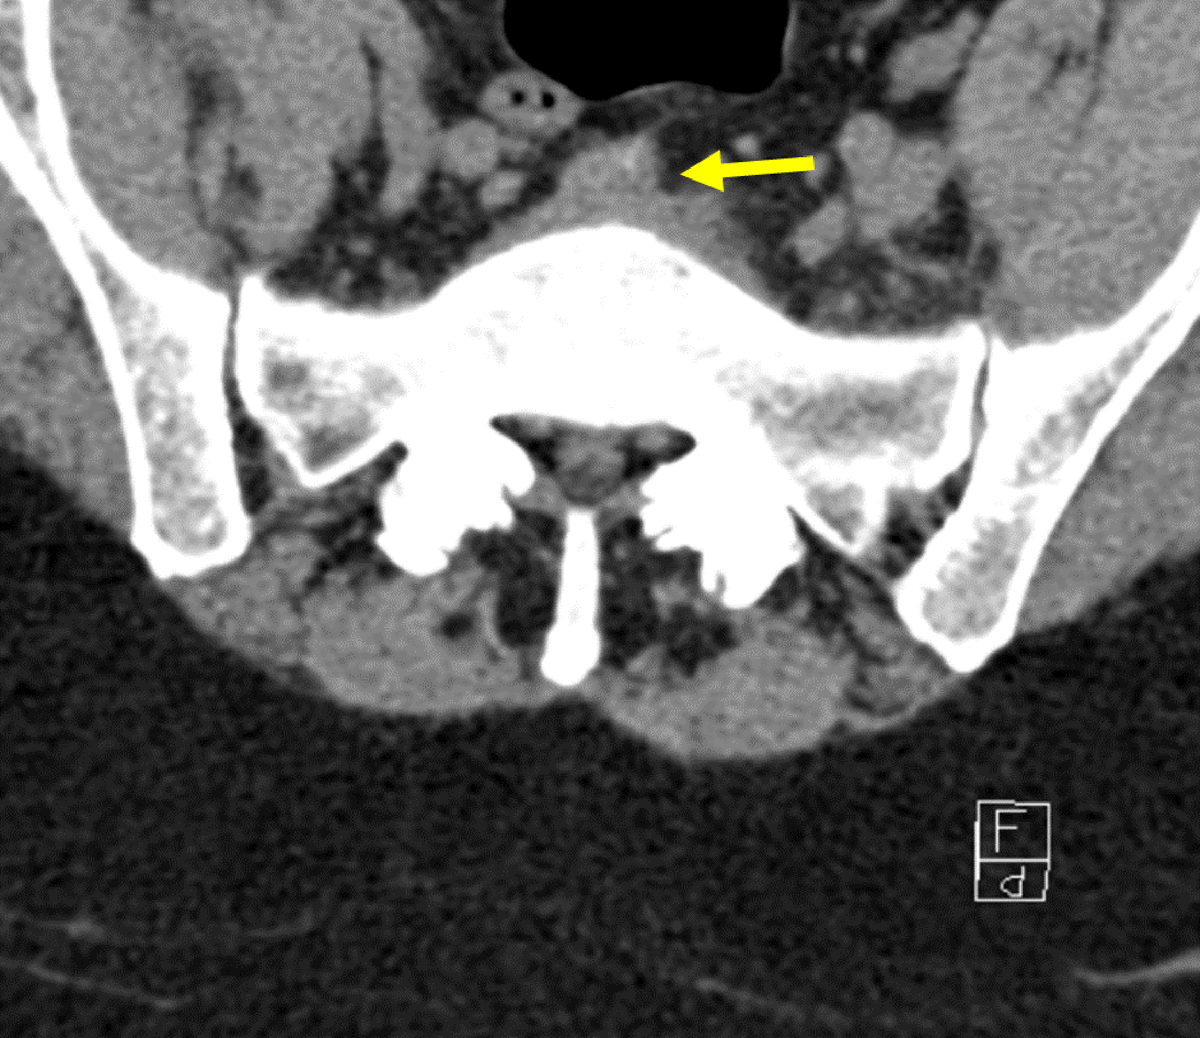

Figure 2

Transverse non-contrast CT of L5-S1 disk: Initial CT-scan showing collection in front of disk.